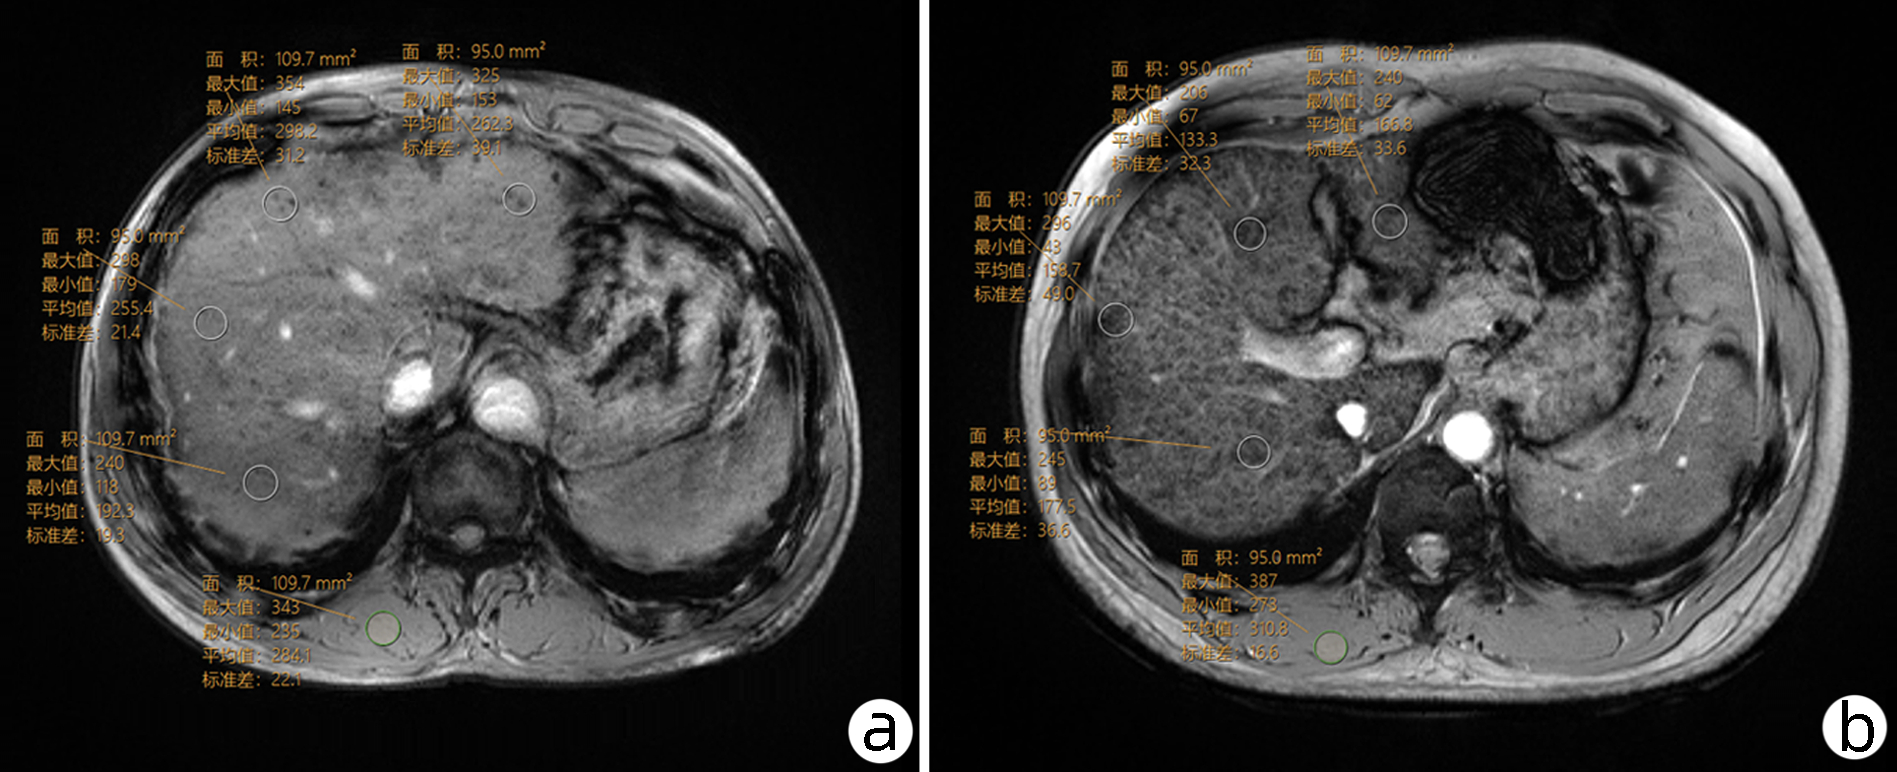

•   Objective  To investigate the value of liver/muscle ratio (LMR) on susceptibility-weighted imaging (SWI) and serum markers in the diagnosis of the severity of chronic hepatitis B liver fibrosis after grouping based on alanine aminotransferase (ALT) level.  Methods  A retrospective analysis was performed for 255 patients with chronic hepatitis B who attended Affiliated Hospital of Yan'an University from October 2018 to September 2021, and the patients were divided into severe liver fibrosis group (SLF group) and non-severe liver fibrosis group (non-SLF group). The SLF group was defined as liver stiffness measurement (LSM) > 9.0 kPa and ALT level within the normal range or LSM > 12.0 kPa and ALT level greater than 1-5 times of the upper limit of normal. LMR was calculated by measuring the mean SWI value of the liver (SWIliver) and the signal intensity of the erector spinae. The t-test was used for comparison of normally distributed continuous data between two groups, and the Mann-Whitney U test was used for comparison of non-normally distributed continuous data between two group; the chi-square test was used for comparison of categorical data between two groups. The binary logistic regression analysis was used to investigate the influencing factors for SLF. The receiver operating characteristic (ROC) curve was used to analyze the diagnostic performance of LMR and its combination with serum markers, and the DeLong test was used to compare the difference in the area under the ROC curve (AUC).  Results  Compared with the non-SLF group, the SLF group had significantly higher ALT (Z=-3.569, P < 0.001), aspartate aminotransferase (AST) (Z=-5.495, P < 0.001), hyaluronic acid (HA) (Z=-6.746, P < 0.001), laminin (LN) (Z=-5.459, P < 0.001), type Ⅳ collagen (Ⅳ-C)(Z=-8.470, P < 0.001), type Ⅲ procollagen (PCⅢ) (Z=-6.326, P < 0.001), aspartate aminotransferase-to-platelet ratio index (Z=-9.004, P < 0.001), and FIB-4 (Z=-8.357, P < 0.001) and significantly lower prothrombin time activity (PTA) (t=10.088, P < 0.001), platelet count (t=9.163, P < 0.001), SWIliver (t=2.347, P=0.02), and LMR×10 (Z=-4.447, P < 0.001). PTA, HA, Ⅳ-C, and LMR×10 were independent influencing factors for SLF. LMR×10 had an AUC of 0.675 (95% confidence interval [CI]: 0.614-0.732) in the diagnosis of SLF, which was significantly higher than that of SWIliver (AUC=0.594, 95%CI: 0.531-0.655) (Z=3.984, P < 0.001). PTA+HA+Ⅳ-C+LMR×10 and PTA+HA+Ⅳ-C had an AUC of 0.937 (95%CI: 0.896-0.966) and 0.905 (95%CI: 0.858-0.941), respectively, suggesting that PTA+HA+Ⅳ-C+LMR×10 had a better diagnostic performance than PTA+HA+Ⅳ-C (Z=2.228, P=0.026).  Conclusion  LMR and serum markers can accurately distinguish SLF after grouping based on ALT level. LMR is a quantitative and objective imaging indicator and is better than SWIliver, and it can also improve the diagnostic performance of serum markers for SLF in clinical practice.